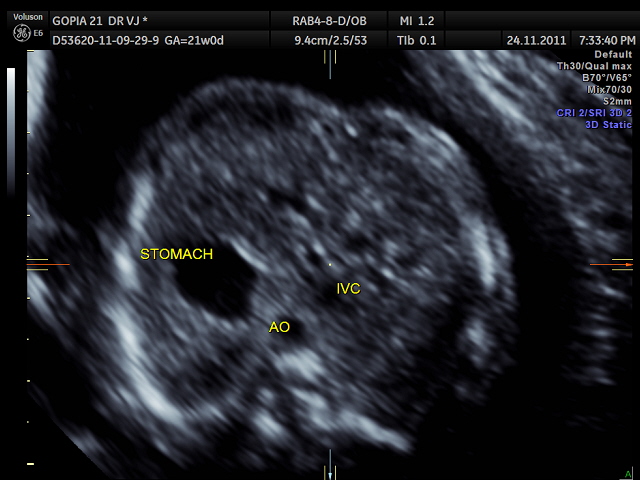

the following two pictures establish the normal situs